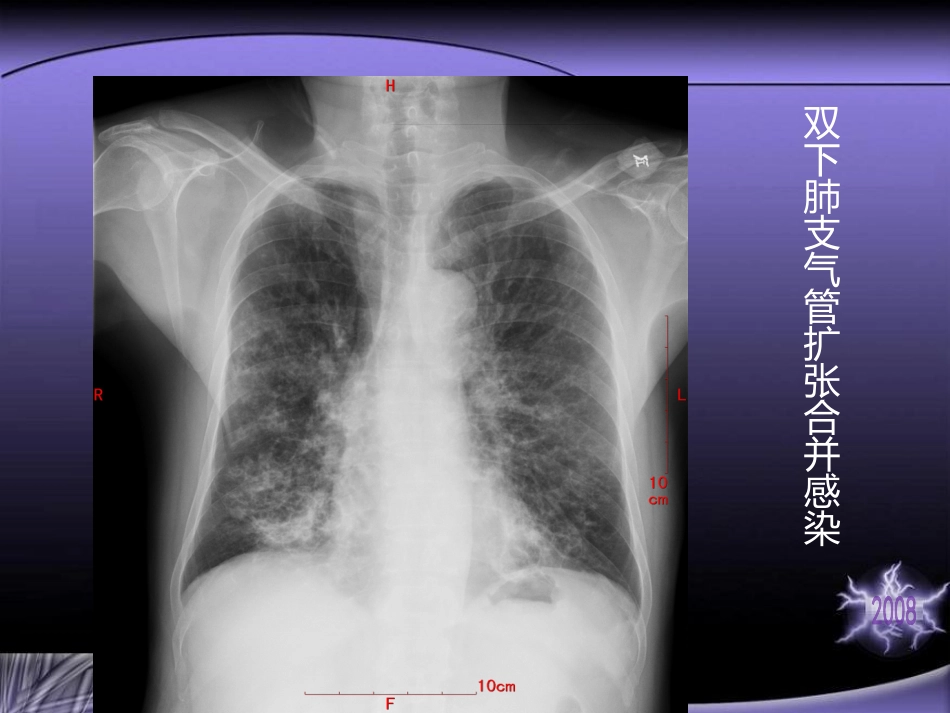

支气管扩张症(Bronchiectasis)以肺内支气管的持续性扩张为特征的慢性疾病,扩张支气管常因分泌物潴留而继发性化脓性炎症。临床上常出现咳嗽、咳大量脓痰,反复咯血等症状·双下肺支气管扩张合并感染左下叶支气管呈轻度柱状扩张(混合型)支气管扩张并感染病因学变迁病因学变迁20世纪70年代以前:小儿肺结核、麻疹、百日咳的发病率较高是造成小儿支气管扩张症的主要原因20世纪70~90年代:非结核性肺炎是引发小儿支气管扩张症的最常见病因(慢性副鼻窦炎、纤毛不动综合症及异物等因素斜位20世纪70年代以后:主要由细菌、病毒性肺炎和支原体肺炎等引起,已见不到肺结核引起的一、支气炎性损管壁的损伤小儿肺结核、麻疹、百日非结核性肺炎损伤了支气管的弹性纤维、平滑肌至软骨等支撑组织或细支气管周围肺组织纤维化牵拉管壁致管壁不能完全回缩支气管腔逐渐发展为永久性扩张肿瘤支气管腔阻塞阻塞性支气管炎支气管遭到破坏异物吸入管外的淋巴结压迫二、支气管先天性发育缺陷和遗传因素二、支气管先天性发育缺陷和遗传因素Kartagener综合症支气管粘膜上皮的纤毛结构及运动异常丧失净化功能易感染鼻窦炎支气管扩张常伴内脏异位支气管扩张症的病理学特点是各种不同病因导致的支气管慢性炎症,并形成不可逆的支气管扩张性损害,其组织病理学相似。一般而言,支气管扩张症有支气管扩张、支气管动脉扩张、支气管粘膜水肿和炎性细胞浸润,粘液栓子堵塞和多发性小侬疡。小儿支气管扩张症的病理肉眼观正常表现:扩张分型:①柱状②囊状③混合型镜下临床病理联系临床病理联系反复继发感染发热、盗汗乏力食欲不振贫血等全身中毒症状。典型症状为慢性咳嗽伴大量脓痰和反复咯血,痰量与体位改变有关。咳痰咳脓性痰慢性炎性渗出和粘液分泌增多并伴继发感染所致反复咯血血管壁遭到炎症破坏及咳嗽所致